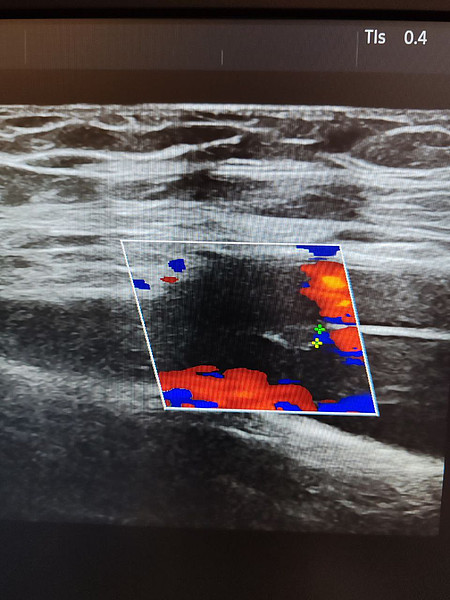

Ежегодно более 32 000 ультразвуковых исследований выполняется пациентам в поликлиниках Кировской клинической больницы №7